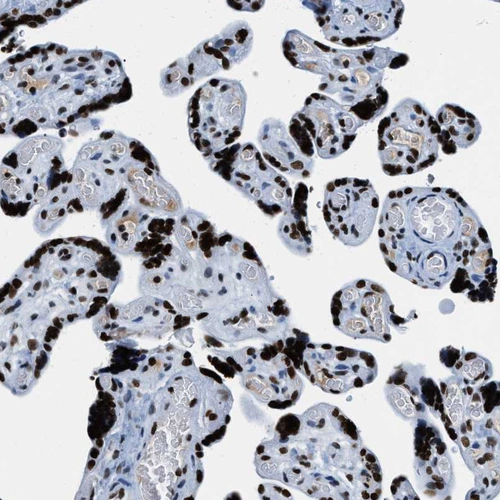

Immunohistochemistry analysis in human placenta and skeletal muscle tissues using HPA019039 antibody. Corresponding TOP1 RNA-seq data are presented for the same tissues.